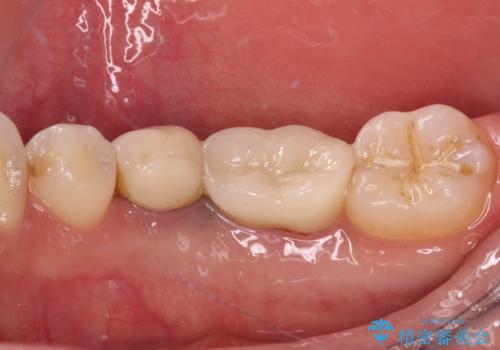

奥歯は抜歯をせずに保存することができました。ただし、状態は決して良いとは言えないため、定期的に経過を見ていく必要があります。